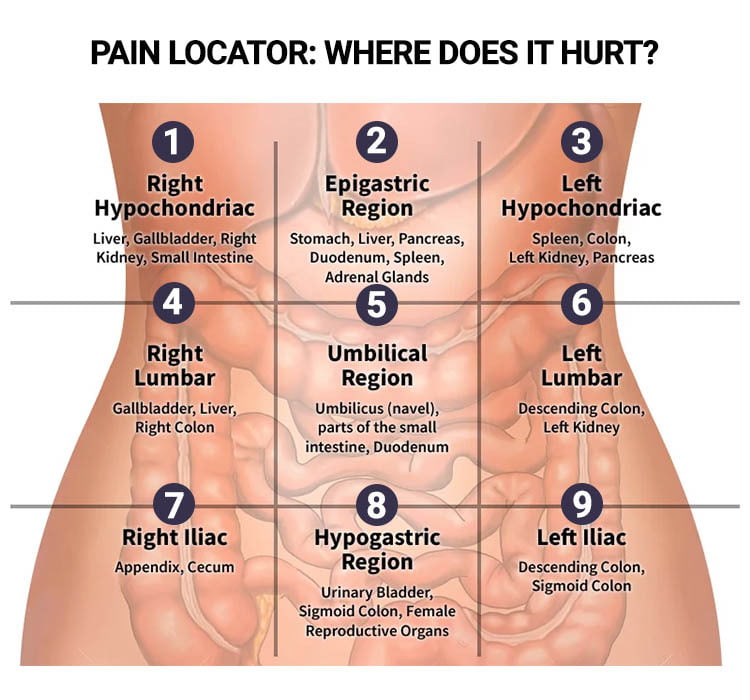

Pin on Abdominal Pain

Causes of Pain in the Right Side | New Health Advisor

Pin on Abdominal Pain Relief | Binders, Braces & Treatments for Stomach …

What Can Cause Right Side Abdominal Pain?

Abdominal and Pelvic Pain in the Nonpregnant Female | Tintinalli’s …

Lower Abdominal Pain: Symptoms And Causes – Forbes Health

Abdominal pain | Health | Pinterest | Pain d’epices and Abdominal pain

Female Abdominal Pain | Types | Symptoms | Causes | Diagnosis | Treatment

What Is Pain In Lower Right Side Of Stomach – StomachGuide.net